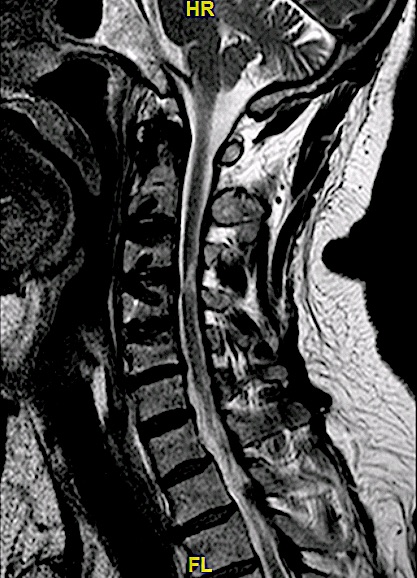

Control de 6 meses

El control postoperatorio RM cervical 6 meses demuestra adecuada descompresión de canal y adecuada aceptación de material de osteosíntesis.